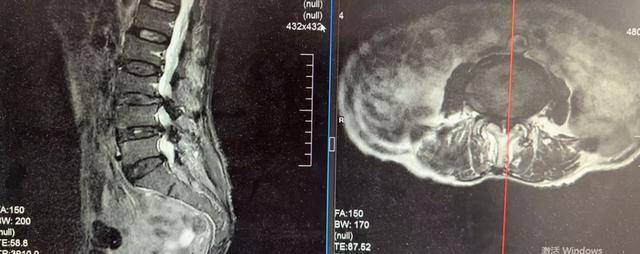

77岁的宋奶奶(化名)因腰椎管狭窄、椎间盘突出,双下肢剧烈疼痛、麻木无力,不仅无法独立行走,连夜间睡觉都无法平卧,生活质量极差。

更棘手的是,她还患有严重的心脏瓣膜病、心律失常等基础病,身体耐受性差。传统开放手术创伤大、风险高,保守治疗又效果甚微,治疗一度陷入困境。

面对复杂病情,澧县中医医院迅速启动多学科联合会诊(MDT),疼痛脊柱科、心血管内科、麻醉科等专家共同评估,最终确定:单侧双通道脊柱内镜(UBE)微创手术是最适合的方案。